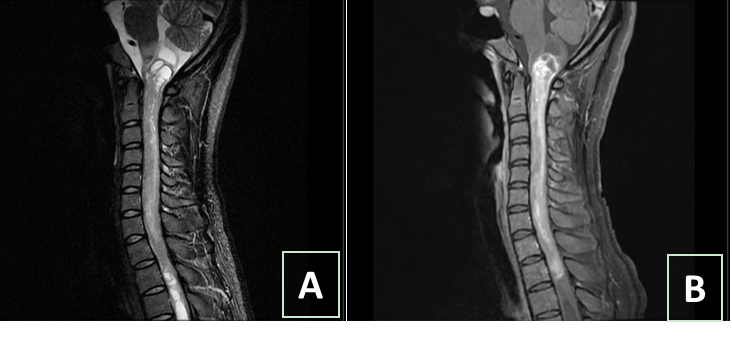

“如今韶华依旧,芳华却已故。”小甜的理想、抱负等等所有的一切,似乎在一瞬间都被病魔无情地撕碎了。室管膜瘤是脊髓肿瘤这种罕见病里相对常见的类型,发病率不足万分之一,慢性起病,呈膨胀性生长,两端可有囊变,目前治疗方案首选手术治疗。临床症状以躯体不适,肢体疼痛、麻木多见,很多病人被误诊为颈椎病。小甜就是如此,直到走路费力,做了颈椎磁共振检查才发现肿瘤,耽误了近两年的时间。她的病变已经上至延髓,累及呼吸循环中枢,严重者可致呼吸心跳骤停,导致病人猝死,下至上胸髓,严重可导致四肢瘫痪。

图1 术前影像:图A示肿瘤两端囊变,延髓受累严重;图B示肿瘤强化明显,血供丰富